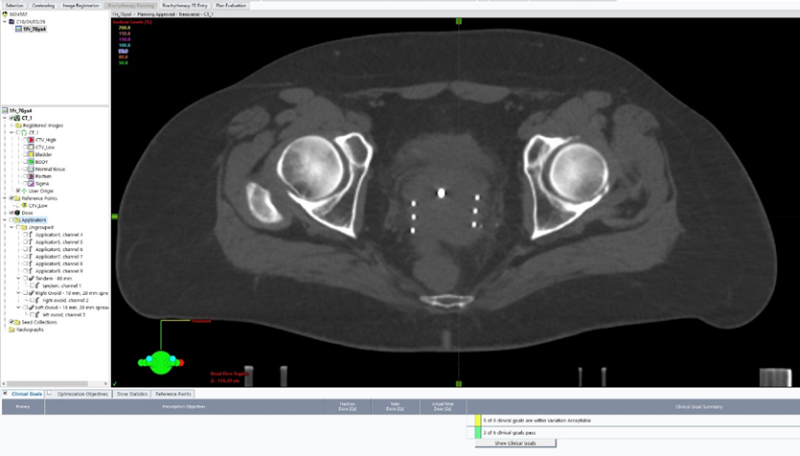

Главная особенность новой методики — адаптивность. Установленное в новом корпусе уникальное оборудование позволяет перед каждым сеансом проводить МРТ или КТ-исследование для оценки актуальных размеров опухоли и планирования брахитерапии.

Как известно, в процессе лечения новообразование может уменьшаться. Благодаря адаптивному планированию доза облучения корректируется под текущие параметры мишени непосредственно перед процедурой. Это позволяет максимально воздействовать на опухоль, при этом сводя к минимуму лучевую нагрузку на здоровые ткани (мочевой пузырь, прямую кишку).

Лечение проводится в режиме высокой мощности дозы (HDR) — свыше 12 Гр в час, что позволяет подвести необходимую дозу радиации точно и быстро, сокращая время процедуры.